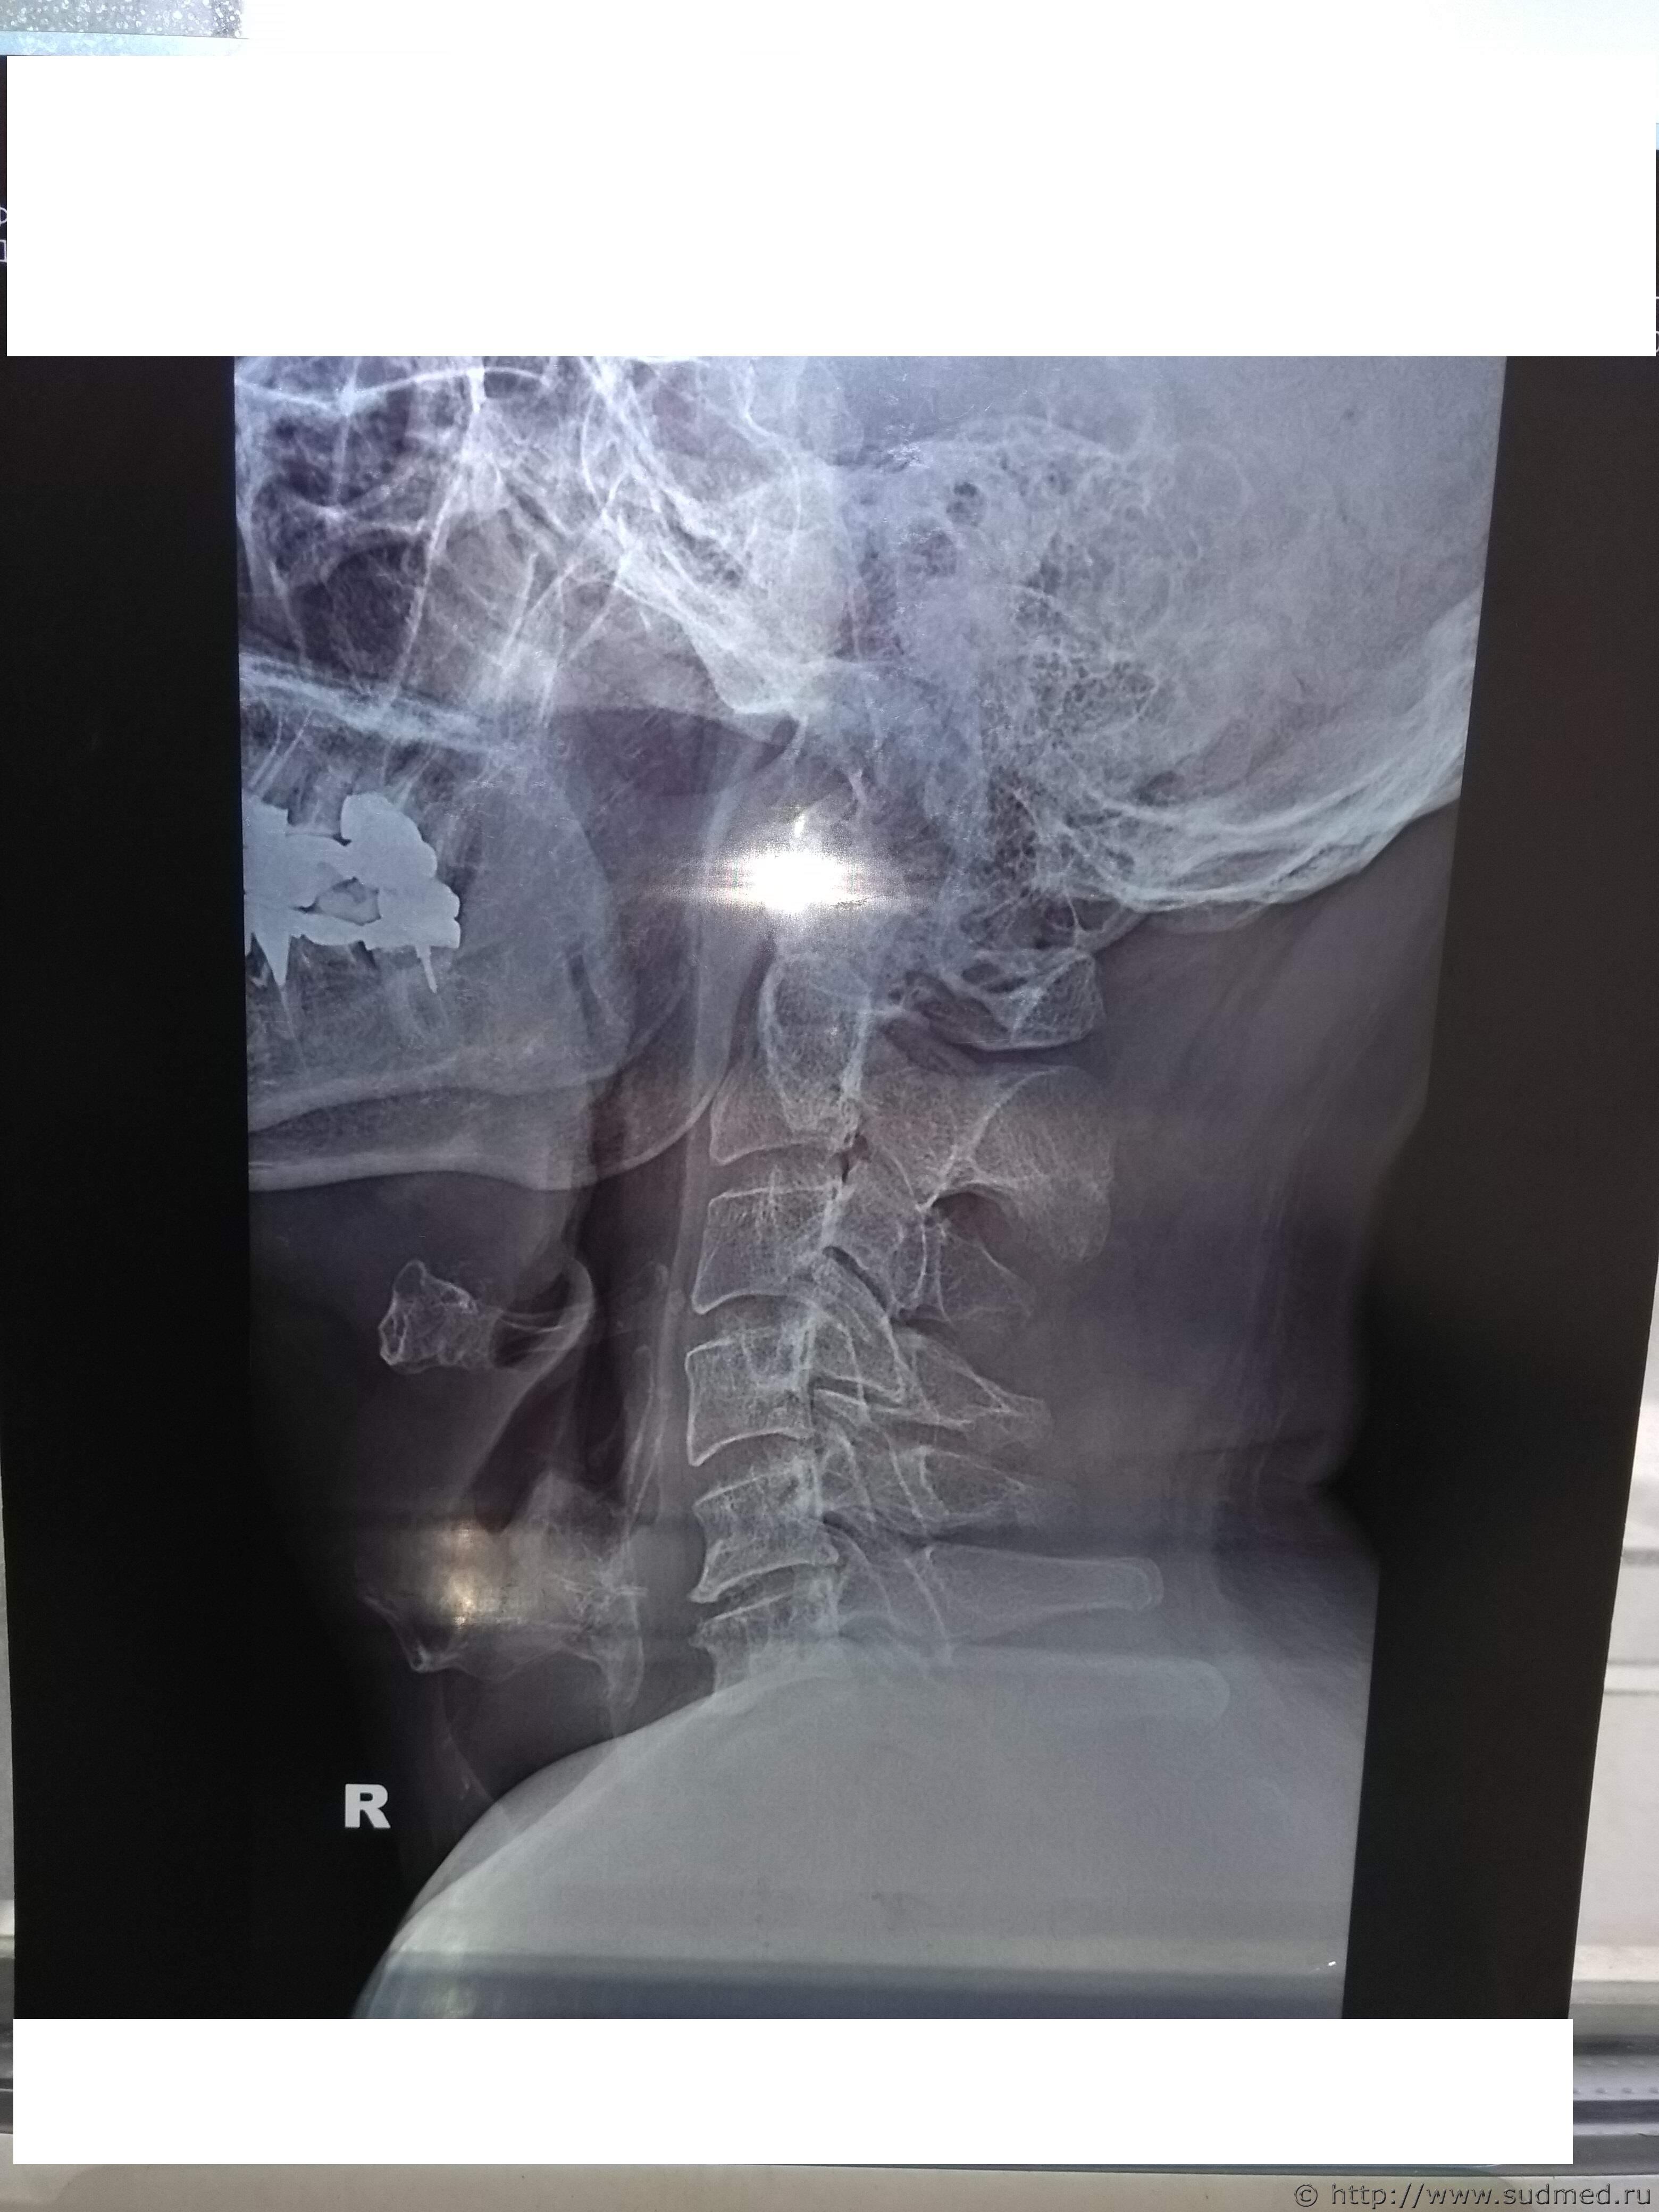

Какие повреждения видны на этой фототаблице?

Похоже на перелом щитовидного хряща, но утверждать не берусь: качество изображений низкое.

А мне кажется там компрессионный 5-6-го, либо перенесенный в анамнезе.